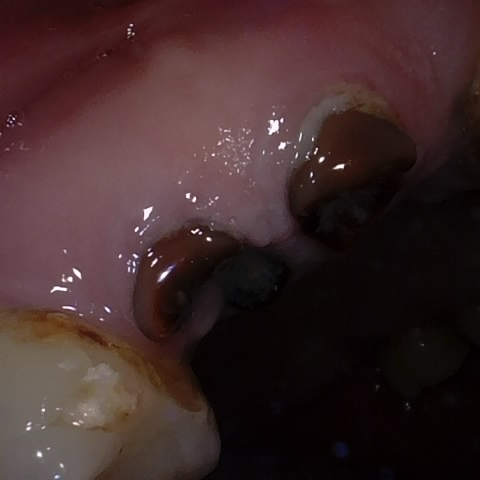

Annotated as "Good"